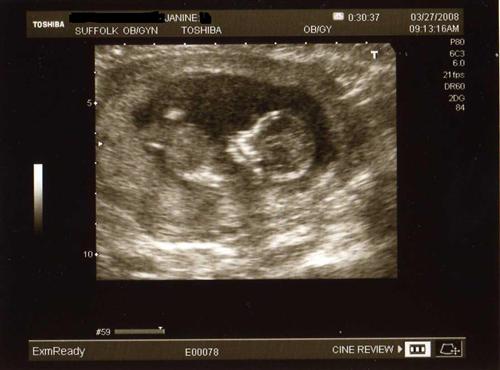

I wanted to share my 12 week sono pics that I had yesterday. Our little one was quite active, as I had a sugery cereal in the morning. Baby was rolling and waving, showing us all five fingers and was rubbing his/her eyes like it just woke up. They said baby looks good and healthy so far.

Another profile pic, heartbeat is 167, and baby is measuring about 3 inches.